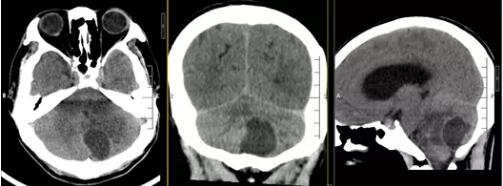

▲术前CT:左侧小脑囊实性占位,周缘水肿,脑组织受压,后颅窝肿胀明显